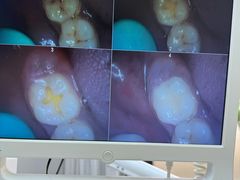

• 牙博士口腔品牌连锁(杨浦店)

• -牙博士口腔品牌连锁(杨浦店)

哀歌_1318 | 25-06-25